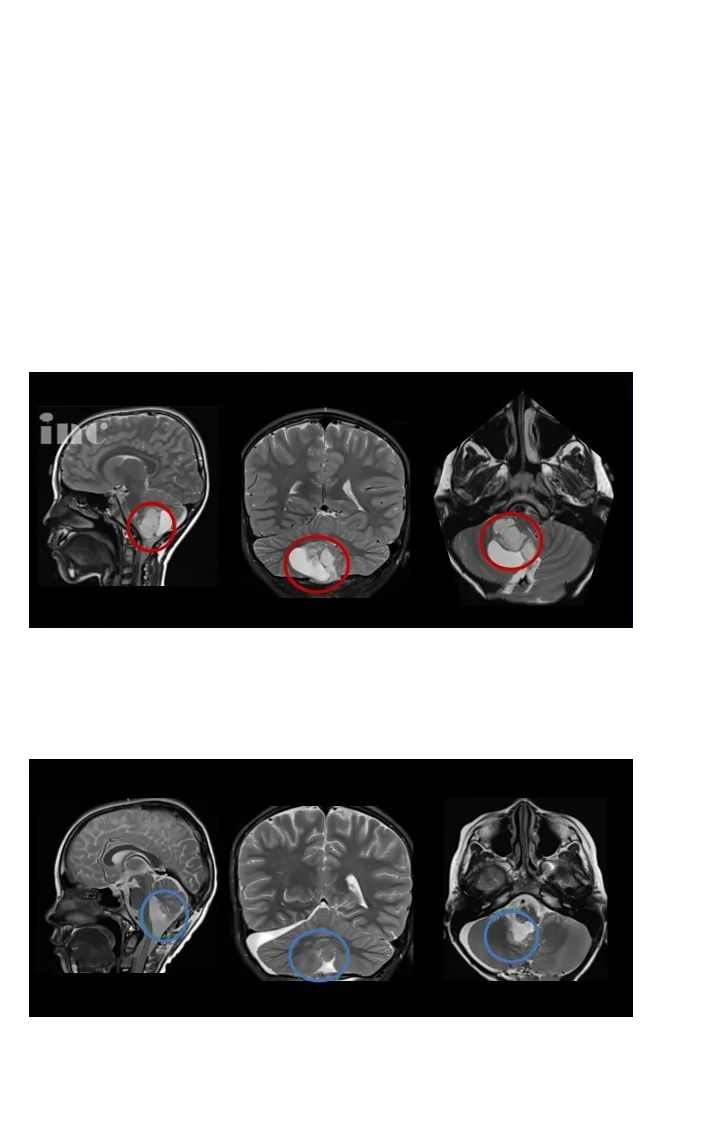

2020年11月,14岁的小永因患脑干-中脑顶盖部位的毛细胞型星形细胞瘤住进医院,MRI影像检查发现松果体区占位伴幕上脑室扩张积水,病灶有明显强化生长迹象。小永父亲在医生朋友的下联系到INC德国巴特朗菲教授进行国际咨询咨询。巴教授表示,小永已有很明显的手术指征,如果能及时接受手术,脑脊液通道可以通过肿瘤的切除而得到恢复。教授凭以往的手术经验判断,可实现神经外科显微镜下手术近全切瘤,且手术风险很低。

收到巴教授的咨询意见回复后,小永父母决定带孩子赴德国接受巴教授的手术治疗。由于肿瘤基底部和脑干关系密切、紧邻小脑,术中教授在保全患者正常功能神经和脑干等重要脑组织的前提下,完成肿瘤近全切手术,术后无新发长期性后遗症。术后1年多回访时,小永父母表示孩子手术后恢复很好,经过康复治疗,现在已经可以正常生活和学习,并正在备战中考,为此感谢巴教授的治疗。